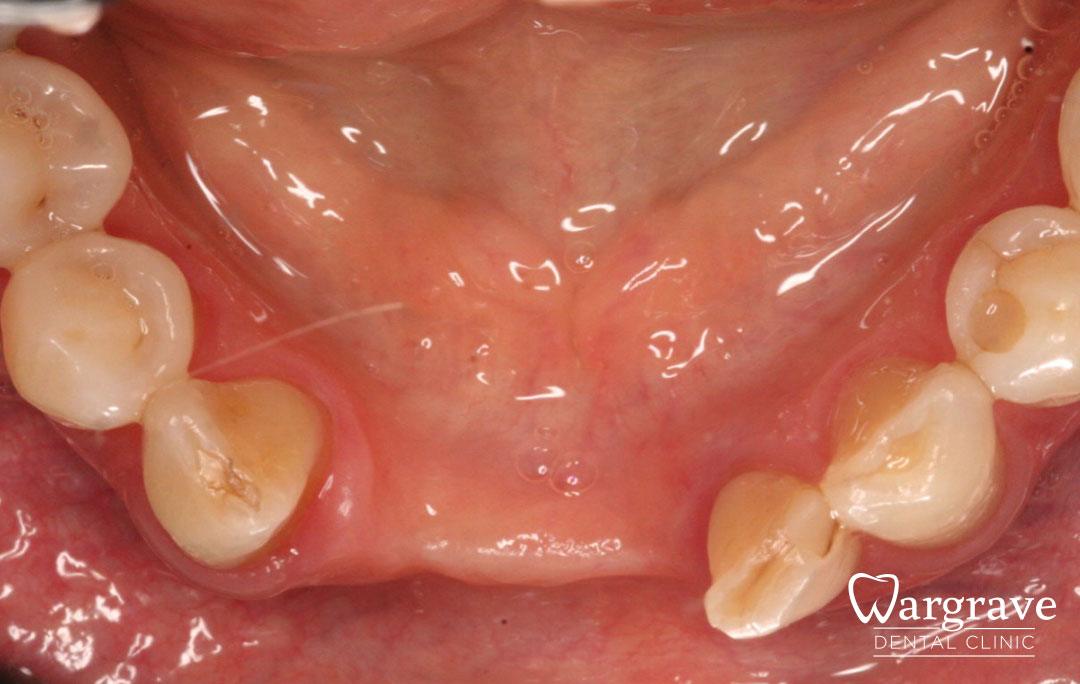

Healthy Smiles These are more advanced examples of different treatments available.All cases shown were carried out by Dr R Khurana unless otherwise stated. Immediate implants Anterior Mandible Bone Regeneration Anterior Mandibular Implant Bridge Maxillary Anterior Implant Bridge Implant stabilised ‘Life Like’ replacement dentures Implant Bridge after 10-years with zero bone loss Implant examples including ZBLC concepts Adhesive Bridge solution for a missing premolar Multidisciplinary care Orthodontics, Replacement veneers and composite bonding Adhesive Bridge solution for missing central incisors Replacement crown, Veneer and Composite Bonding Replacement Crowns and Veneer Injection Moulding using Composite Resin Equilibration Tooth Whitening to treat Developmental Discolouration